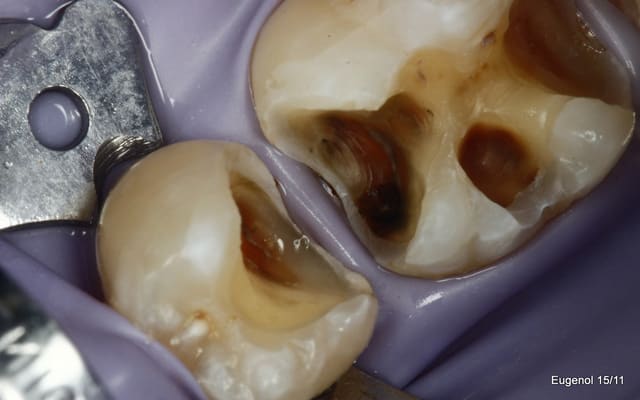

un truc que je fais souvent, quand je monte deux compo volumineux en contact, je monte le plus gros et difficile sans matrice et comme ça j'ai accès a la marge, et je peux donner une jolie forme galbée proximale

puis je monte le suivant avec une seule matrice...

plus facile je trouve d'avoir le point de contact